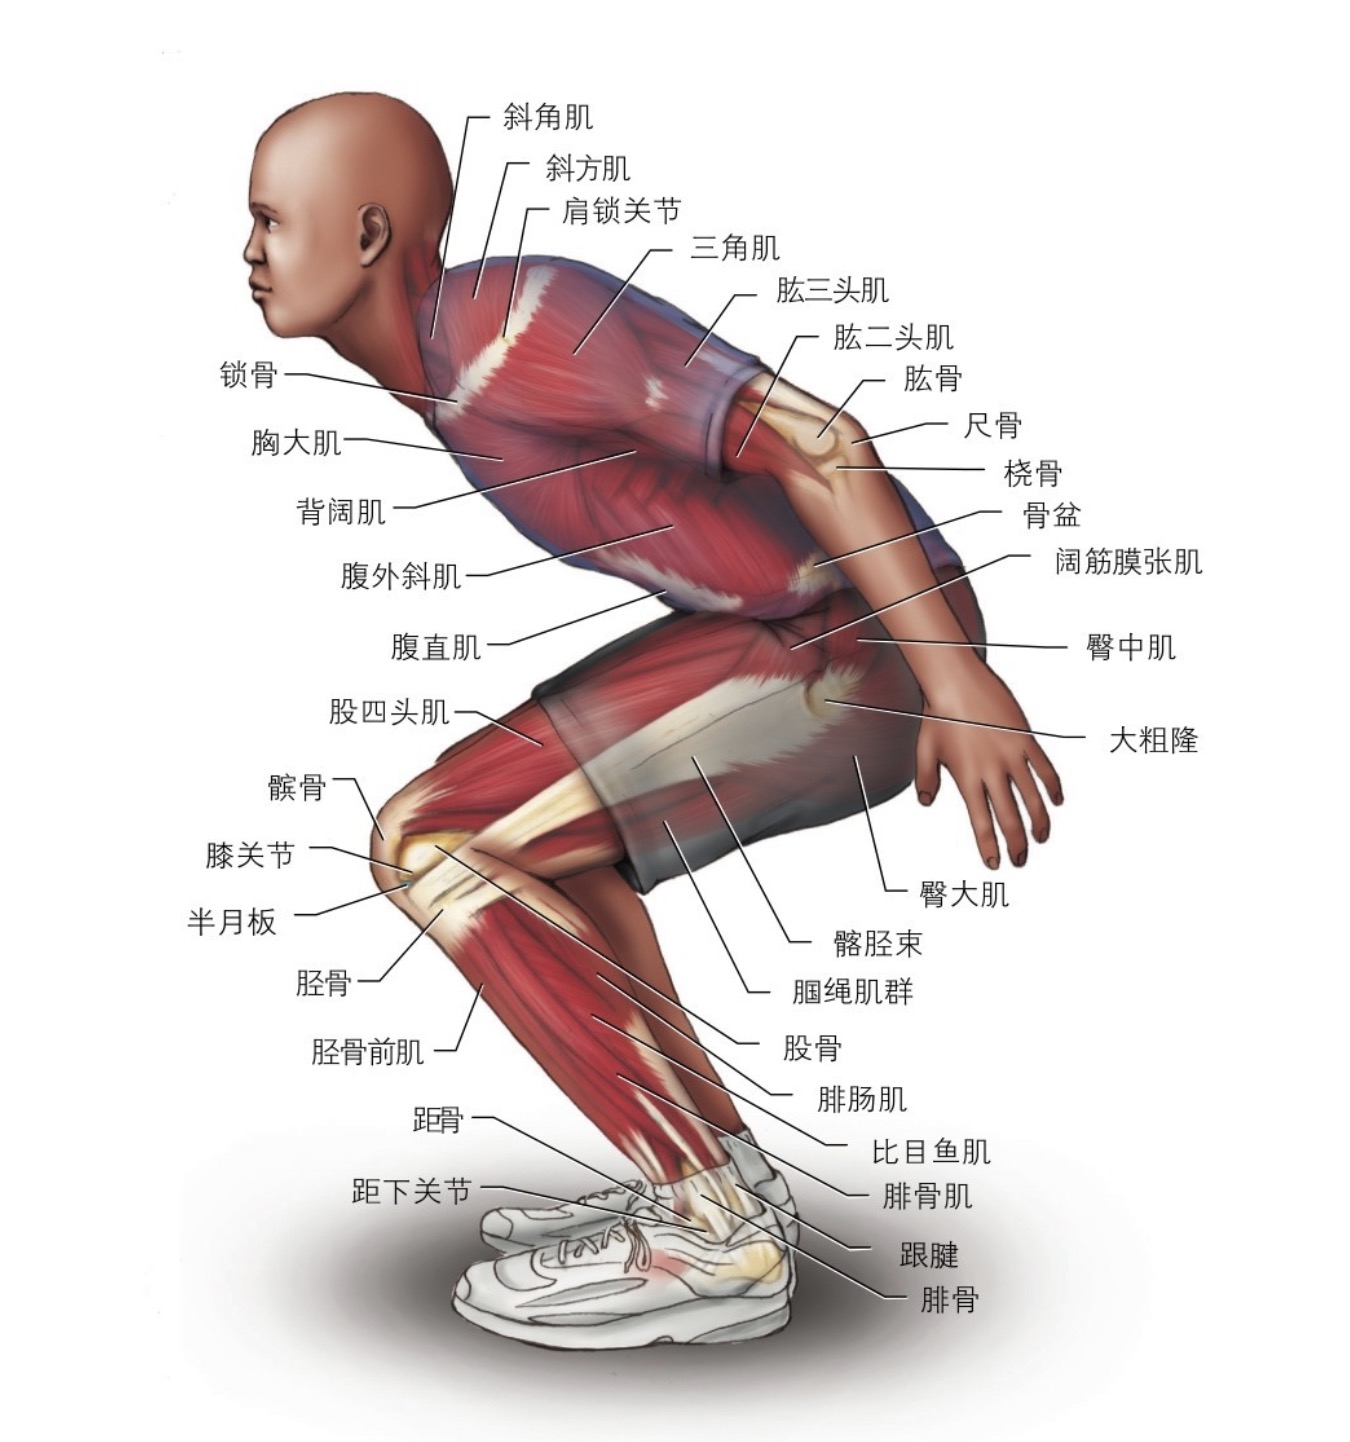

- ����Ƥ�������뼹������ĺ���ģʽѵ�� ���Ǽ�������������� ��2020-02-27

- ��������ĺ�����ѧ��������һ���ض������ƽṹ�¾����������ﵽһ���ȶ�״̬���ں���ʱ���������ƫ����������������������������о��������������仼�����۽��й��������ƣ� ��������������������Σ�����أ���������������ȣ��������仼��ӵ�и��ߵ���ɱ����������ʣ�������ʹ���߶�֧�����Ƶȷ������Ʒ���˳Ӧ����.....